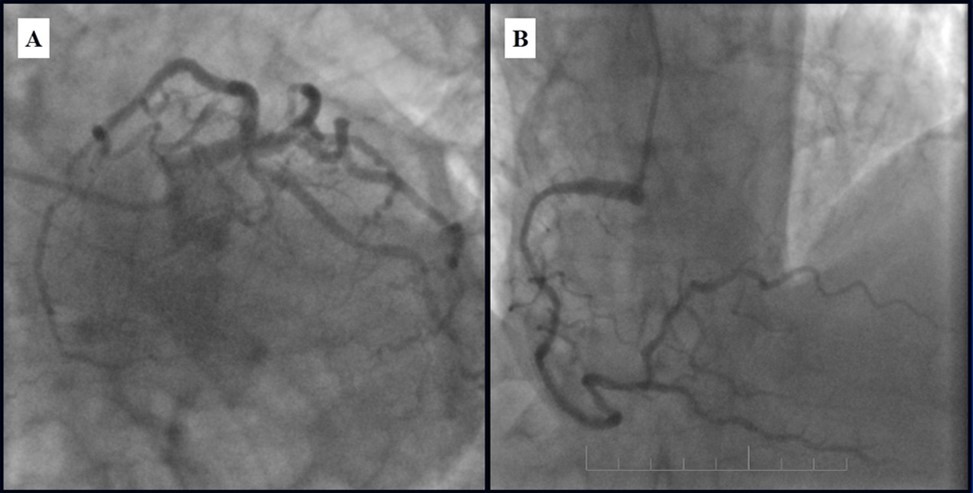

Subsequent coronary angiography eight months after the last PCI revealed patent stents with mild, non-significant restenosis in DES and 50-60% in-stent restenosis in BMS (Figure 13, Figure 14).

Figure 13.Subsequent CAG eight months after last PCI; A - Patent stents with mild, non-significant restenosis in left coronary artery; B - 50-60% in-stent restenosis in RCA.

Subsequent  CAG eight months after last PCI; A - Patent stents with mild, non-significant restenosis in left coronary artery; B - 50-60% in-stent restenosis in RCA.

Figure 14.Left coronary artery, follow-up CAG eight months after last PCI.

Left coronary artery, follow-up CAG eight months after last PCI.